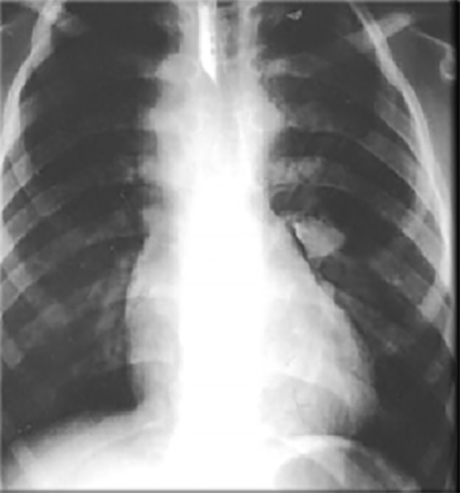

This chest X ray shows right ventricular hypertrophy, a small pulmonary trunk and decreased pulmonary arterial vascularity.

Right ventricular hypertrophy is suggested by the upturned cardiac apex.

A small pulmonary trunk is suggested by the absence of cardiac density beneath the aortic knob, resulting in a straight edge of the upper left cardiac silhouette.

Decreased pulmonary arterial vascularity is suggested by the small size of the central pulmonary arteries shadows and absence of distal arterial markings. This chest X ray is consistent with tetralogy of Fallot.